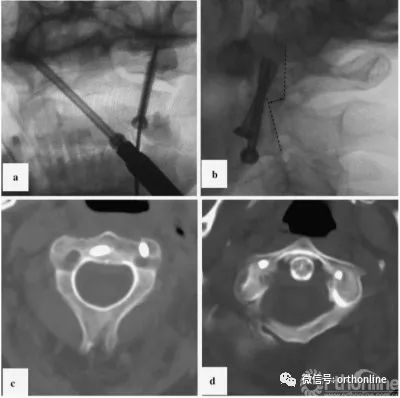

图3

图3病例1:固定时x线及对照CT扫描;a、使用对侧轨迹将克氏针置入右侧侧块;b、左侧单侧后路经关节固定;c、开口位x线;d、置钉后的三维CT扫描图片(轴位);螺钉位于寰椎两侧的侧块,左侧为双皮质;CT,计算机断层扫描

Fig. 3 Case 1: X-ray images of the fixation stages and control CT scan. a K-wire insertion into the right lateral mass using a contralateral trajectory. b Left-sided unilateral posterior transarticular fixation. c Control X-ray in the transoral plane. d CT scan control after screw insertion (axial plane). Screws are located in the lateral masses of the atlas on both sides and are bicortical on the left side. CT computed tomography